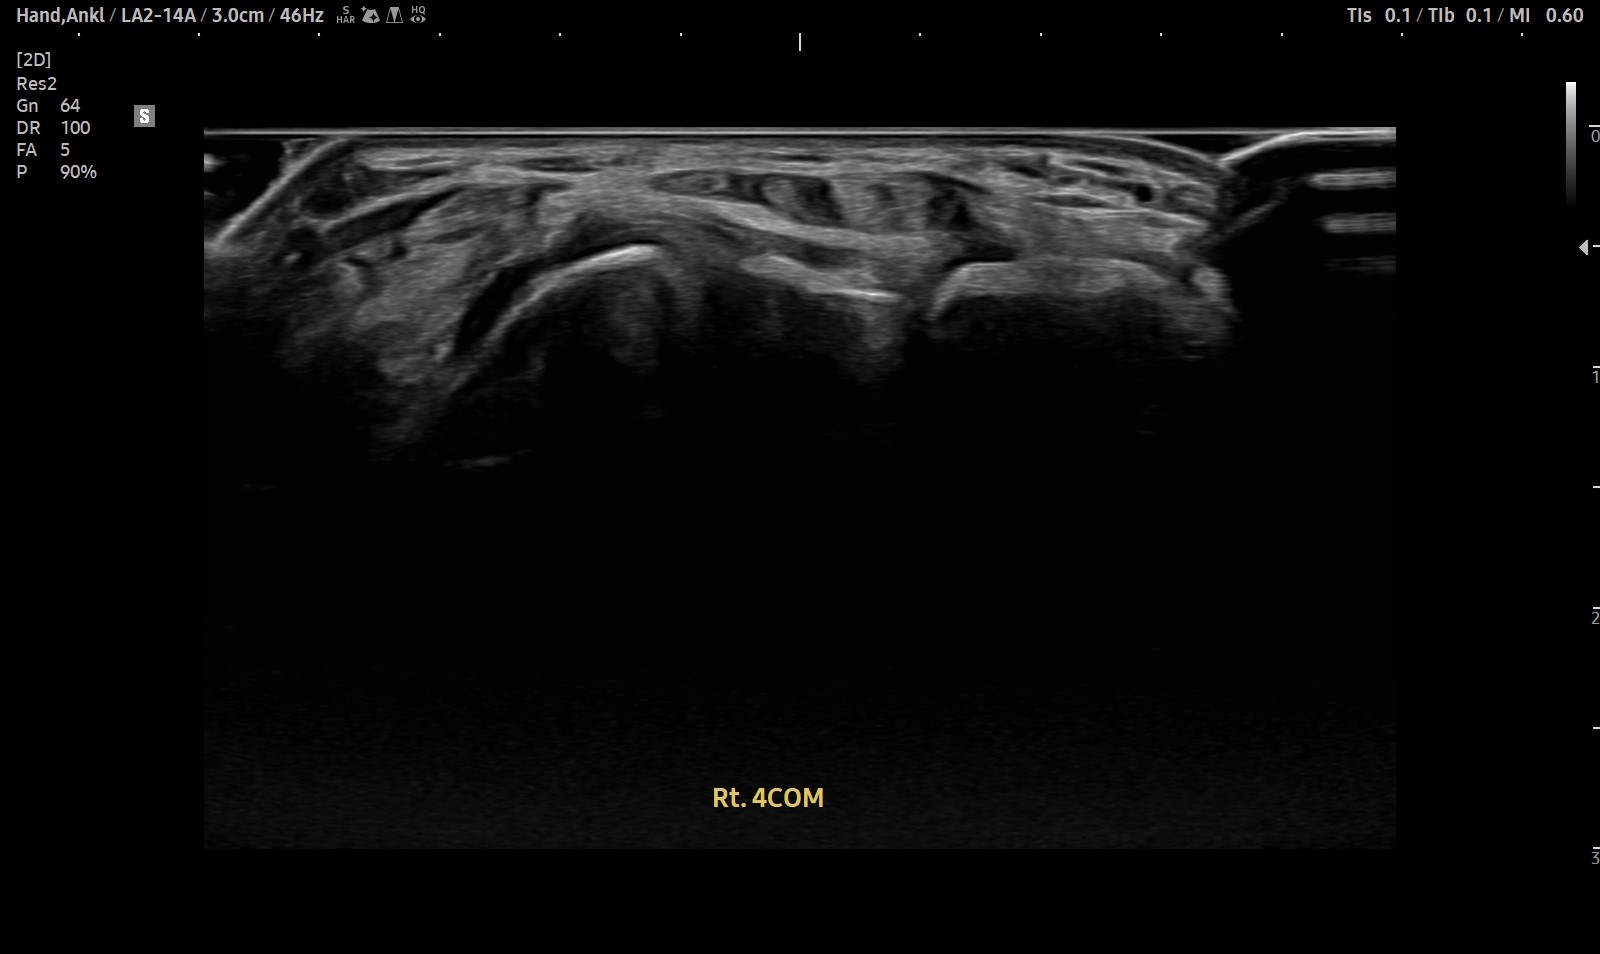

- 치료기간 : 2025. 7 . 4 ~ 2025 . 9 .1

- 치료횟수 : 10 회 (2cycle)

치료 전

치료 후